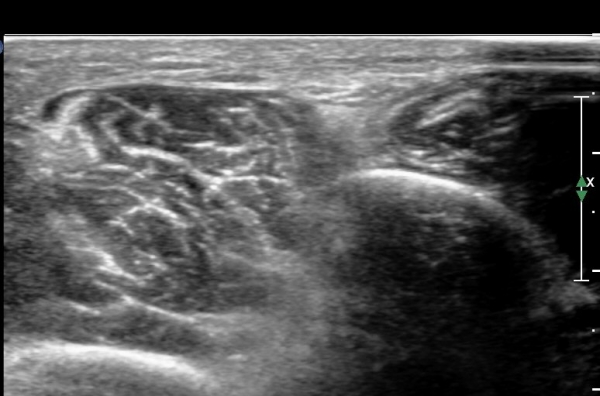

¾ÕÂÊ ¸»´Ü °æ°ñºñ°ñ°üÀý ¾à 5cm ±ÙÀ§ºÎ Ⱦ´Ü몀°Ë»ç ½Ã õºñ°ñ½Å°æ Àü¸é¿¡ Àú¿¡ÄÚ ³¶Á¾¿¡ ÀÇÇÑ ½Å°æ ¾Ð¹ÚÀÌ °üÂûµÈ´Ù(ÀÌ °üÂûµÈ´Ù(»çÁø 6, 7).

¸»´ÜÀ¸·Î °¥ ¼ö ·Ï ³¶Á¾ÀÌ Ä¿Áø°í õºñ°ñ½Å°æ ¾Ð¹ÚÀº ½ÉÇØÁø´Ù(»çÁø 8).